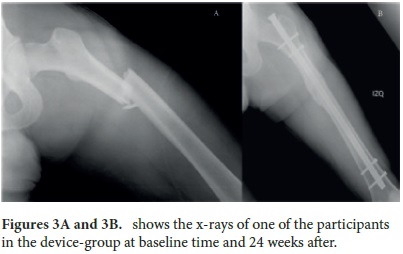

In all cases, the fracture was surgically treated within the first 10 days from the initial trauma, but only for 21 patients (33%) was it treated during the first 48 h. All surgeries were planned as a closed reduction and intramedullary nailing, but 23% needed an open reduction of the fracture, with no difference between groups. In all cases, the nail was reamed and blocked both proximally and distally. Figures 3A and 3B show a patient with a femoral fracture in the device-group at day 1 and 24 weeks after surgical treatment with this kind of nail. No infections or complications related to surgery or to the use of the devices were apparent.